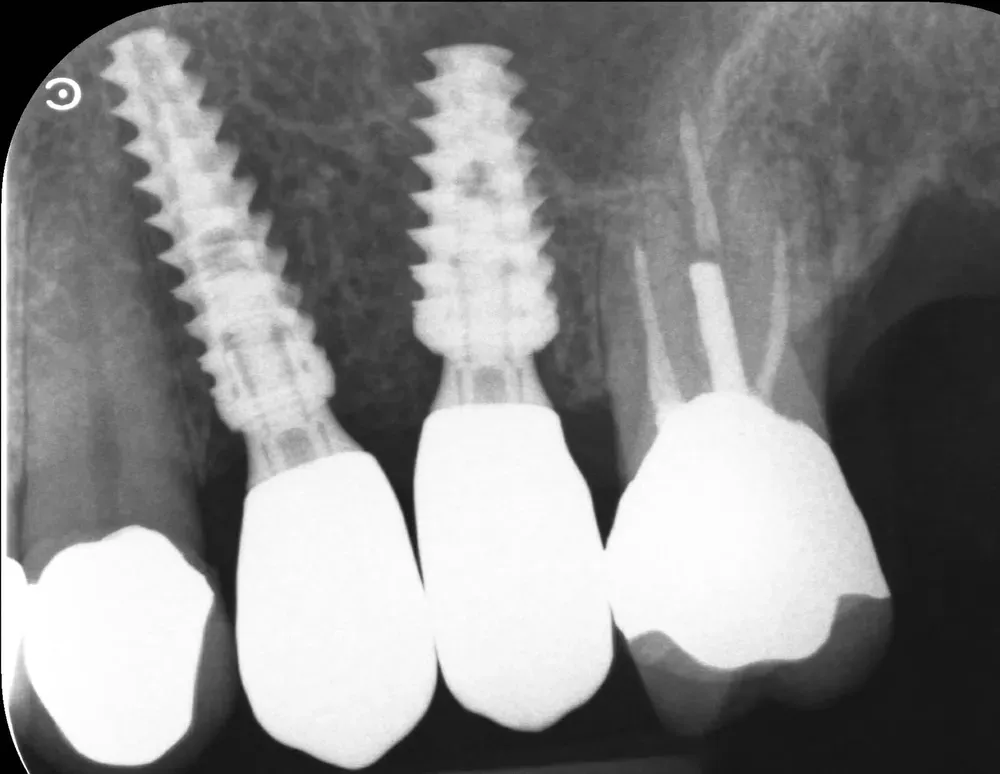

Di seguito, le radiografie periapicali mostrano gli impianti appena inseriti e gli abutment con i provvisori.

Rx Periapicale Post-op

Rx Periapicale con abutment e provvisori

Passati tre mesi, abbiamo effettuato una scansione per realizzare le corone in zirconia. L’ultima radiografia è stata scattata il giorno della consegna delle corone.

L’aumento della densità ossea intorno all’apice dell’impianto in posizione 2.5 è evidente, particolarmente in zona mesiale. In quella zona, la corticale del seno si è sollevata maggiormente.

Rx periapicale alla consegna delle corone in zirconia